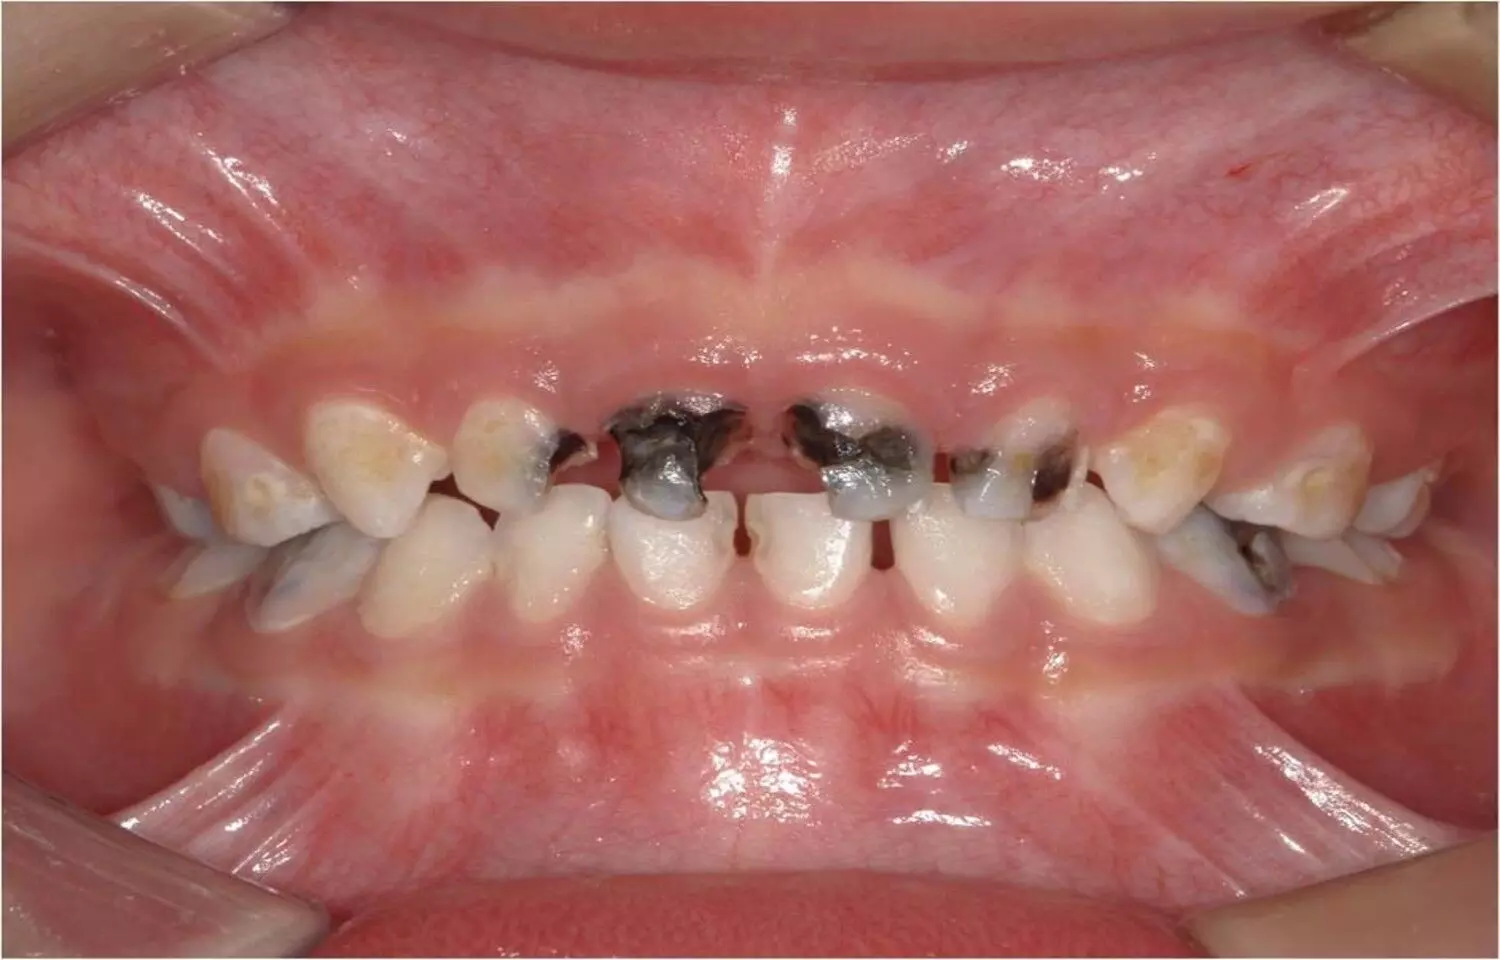

A new study published in BDJ Open has found that adopting evidence-based early feeding practices—such as reducing sugar exposure, ensuring timely introduction of complementary foods, maintaining consistent vitamin D supplementation, and promoting dietary diversity—plays a critical role in preventing early childhood caries (ECC). The findings reinforce the strong link between nutrition during infancy and long-term oral health outcomes. Researchers analyzed feeding behaviors, dietary patterns, and oral hygiene practices in young children to understand how early-life nutrition influences caries development. The study found that frequent sugar consumption, including hidden sugars in processed foods and sweetened milk formulas, significantly increases caries risk—even before teeth fully erupt. In contrast, infants who received breast milk or unsweetened formulas, along with balanced complementary foods, showed better oral health outcomes and fewer lesions.The timing of introducing solid foods also emerged as a key factor. Children who transitioned to complementary feeding at the recommended age (around six months) demonstrated healthier dental development and improved chewing habits, which aid in saliva production—a natural protective factor against caries. Vitamin D supplementation was another protective element, supporting enamel mineralization and resistance to decay.Researchers emphasized that early oral health education should be integrated into pediatric care and parental counseling. Teaching caregivers about sugar-free feeding options, proper bottle use, and early toothbrushing habits could dramatically lower ECC rates. Moreover, community-level nutrition programs and healthcare provider training can help address persistent misconceptions—such as the idea that baby teeth are “temporary” and don’t require care.